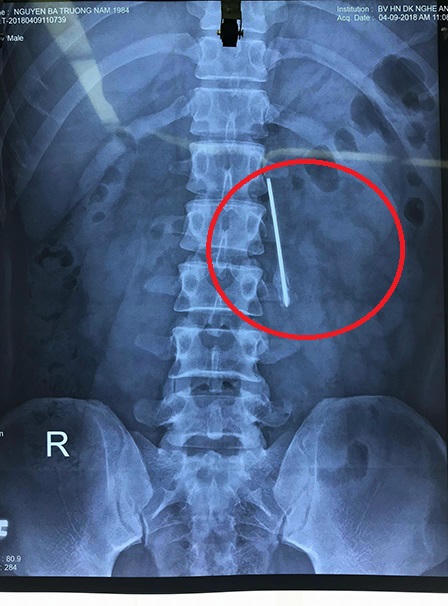

Trước đó, ngày 9/4, Bệnh viện tiếp nhận bệnh nhân Nguyễn Bá Trường Nam (34 tuổi, ngụ tại thành phố Vinh, Nghệ An) với biểu hiện đau nhói và đau nhiều vùng lưng sau khi thi đấu thể thao. Qua thăm khám và hình ảnh chụp phim X-quang, các bác sĩ khi phát hiện hình ảnh dị vật kim khí dài, mỏng nằm chéo vùng cột sống thắt lưng bệnh nhân.

Theo bác sĩ Hoàng Kim Tuấn, Phó khoa phẫu thuật thần kinh cột sống (Bệnh viện đa khoa Nghệ An) cho biết, lưỡi dao này nằm ở vị trí nguy hiểm, sát động mạch chủ bụng, chỉ cần bệnh nhân vận động mạnh có thể khiến nó di chuyển, gây tổn thương mạch máu, ảnh hưởng đến tính mạng nhanh chóng. Ngoài ra, vết gỉ sét của lưỡi dao có thể gây áp xe, viêm nhiễm nguy hiểm nếu ở lâu trong cơ thể.